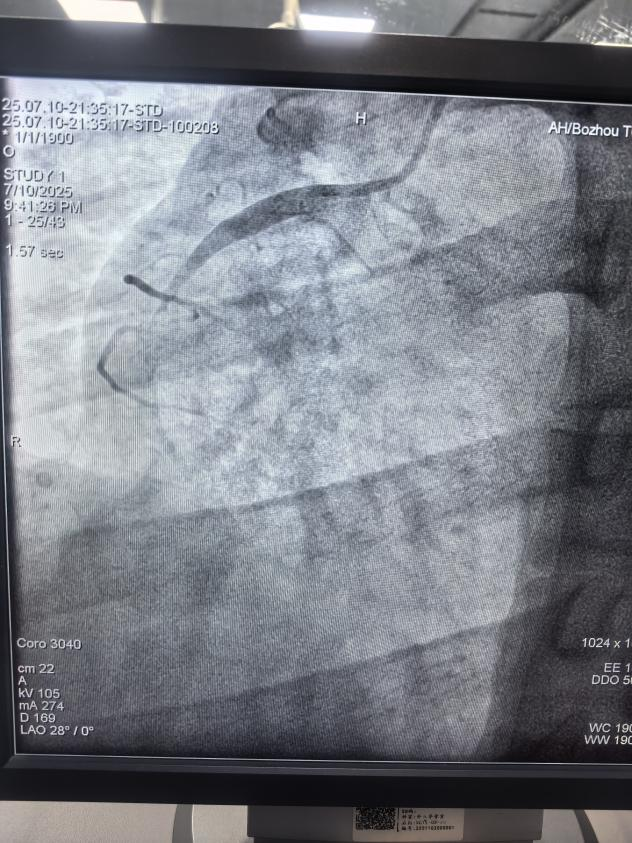

患者馮先生身高170cm,體重95kg,體型較為肥胖,平時(shí)作息不規(guī)律,長(zhǎng)期抽煙、飲酒、熬夜,當(dāng)天突發(fā)心前區(qū)疼痛持續(xù)不能緩解,伴有大汗淋漓、煩躁不安,通過(guò)呼叫120救護(hù)車(chē)送至我院胸痛中心。心血管病科二病區(qū)介入醫(yī)生給他做了急診冠脈造影檢查,顯示右冠狀動(dòng)脈近段急性完全閉塞。經(jīng)過(guò)手術(shù)醫(yī)生積極有序的救治,順利開(kāi)通閉塞血管后,在血管內(nèi)超聲指引下精確植入一枚藥物洗脫支架,植入后血流恢復(fù)良好,馮先生癥狀明顯改善,生命體征逐漸平穩(wěn)。術(shù)后身體恢復(fù)良好,于7月20日順利出院。

右冠急性閉塞

支架植入后,血管流通